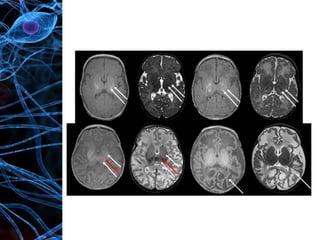

• Neuroimaging

 Cranial ultrasound: Not the best in assessing

abnormalities in term infants. Echogenicity develops

gradually over days

 CT: Less sensitive than MRI for detecting changes in

the central gray nuclei

 MRI: Most appropriate technique and is able to show

different patterns of injury. Presence of signal

abnormality in the internal capsule later in the first

week has a very high predictive value for

neurodevelopmental outcome